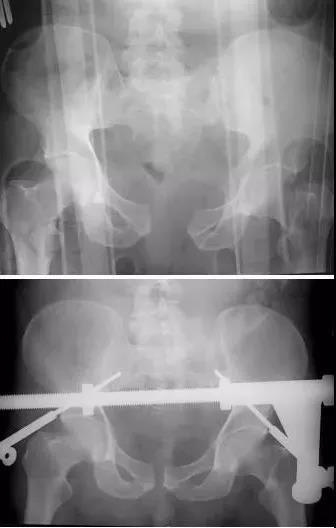

2)骨盆骨折

30min,三个决定:

- 开放性骨折,立即止血;

- 骨盆制动(10-15min);

- 观察10-15min,血流动力不稳定,能否手术?

血流动力学稳定,在7天内手术?